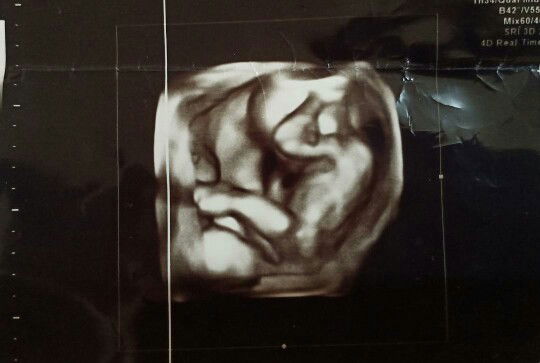

Excited to become a mum